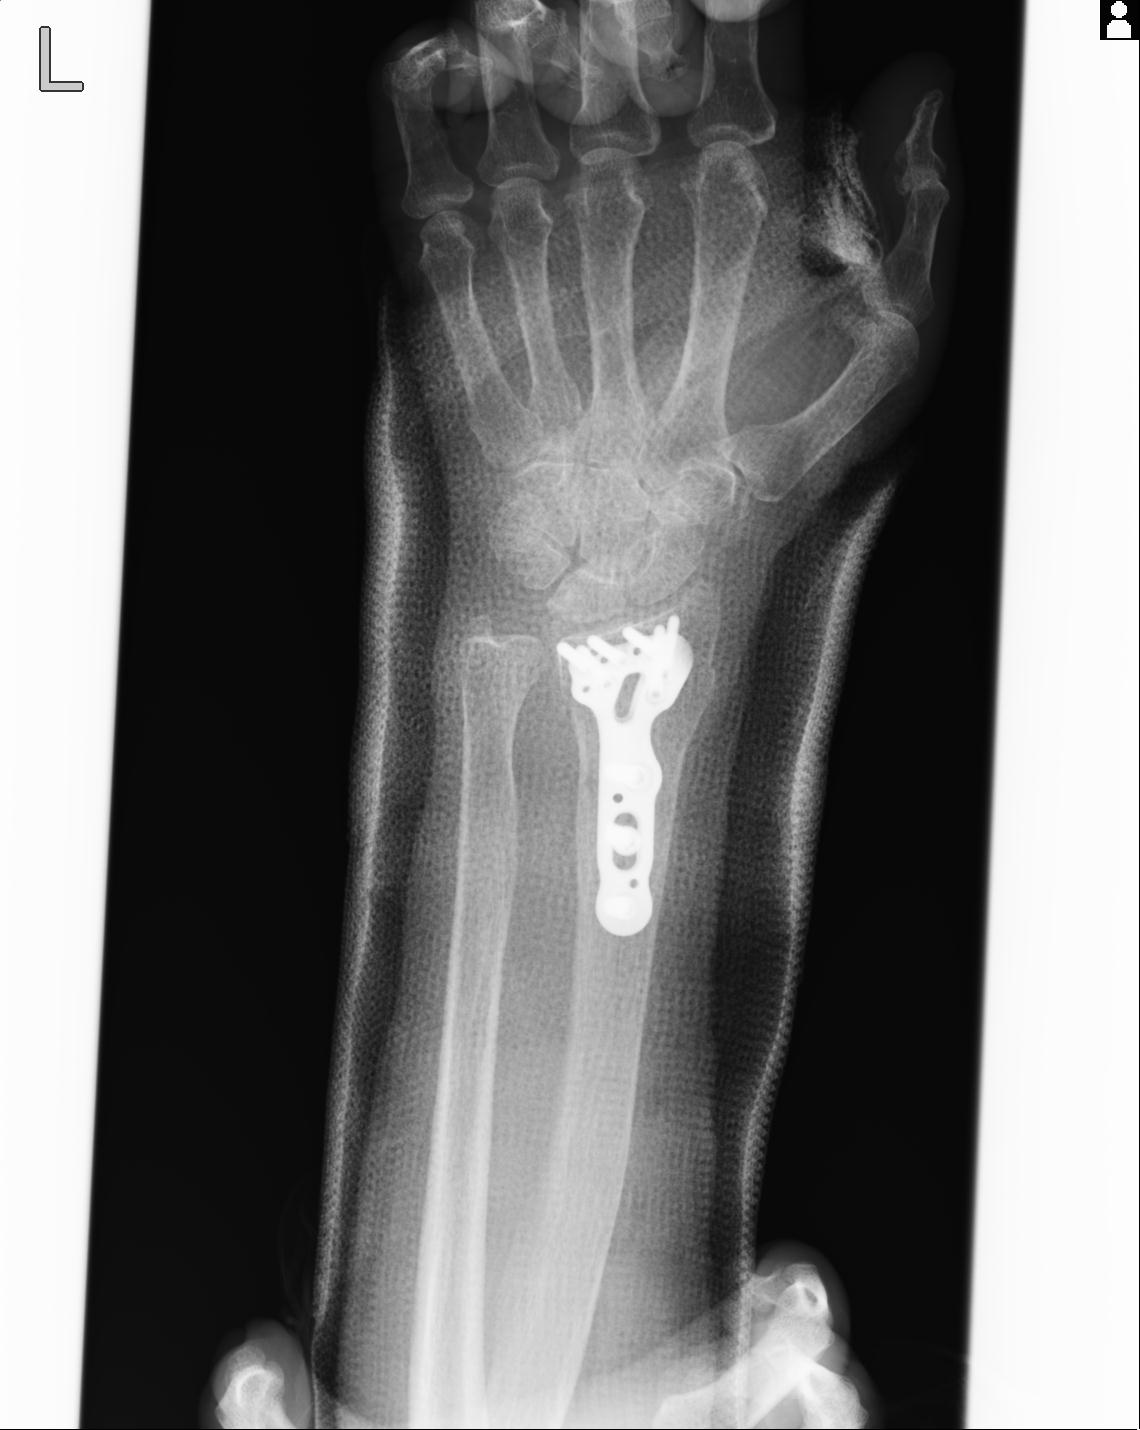

102766 1/5 1/12 左手関節 4R 28歳男性 左橈骨遠位端